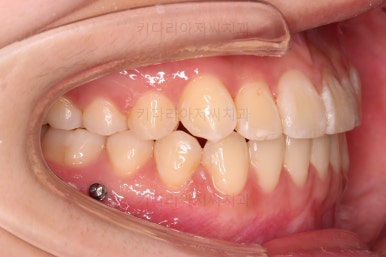

자칫하면 비발치 시 입이 튀어나오는 경우가 있어요.

삐뚤다는 건 자리가 부족하다는 뜻인데 부족한 자리를 확보 안해주고 억지로 가지런하게 하다보면 치아가 앞으로 튀어나오게 되거든요.

그래서 비발치로 하더라도 본인이 만족할만한 수준까지 입이 나오지 않도록 미니스크류를 병행해서 사용하여 통째로 뒤로 당겨주기로 했습니다.

옆라인도 입이 안나오게 비발치 교정 마무리 잘 되었고요.

묘하게 옆라인의 곡선이 더 예뻐졌죠?

이상 미니스크류를 이용해 비발치로 덧니 치아를 교정치료한 사례였습니다.